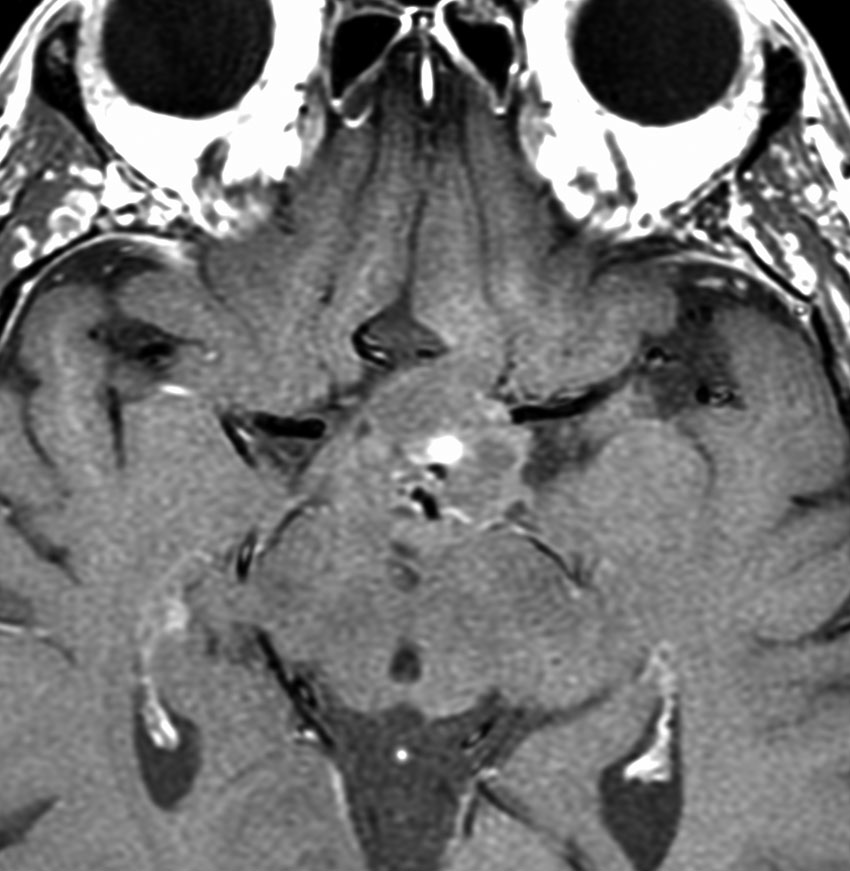

思春期の女の子にできた小脳腫瘍です。とても大きく見えますがほとんどが水たまり(のう胞といいます)。第4脳室が腫瘍で圧迫されて閉塞性水頭症になりました。のう胞の中に出血がありますが毛様細胞性星細胞腫では腫瘍内出血をしばしば見ます。右の写真で脳室が大きくなっています。こんなに大きいのに小脳症状は全くなくて,頭痛と嘔吐が症状でした。

赤で塗ったところだけが毛様細胞性星細胞腫です。これを取れば治ります。簡単な手術ですし後遺症も残りません。

手術後のMRIです。水頭症も改善してますから症状も消失しましたし,すぐに退院です o(^o^)o

2歳の時に歩行障害で転倒しやすくなって発症しました。巨大な小脳虫部の毛様細胞性星細胞腫です。後頭下開頭で亜全摘出して,翌年,残っていた小さな残存腫瘍を全摘出しました。

cerebellarpilo3cerebellarpilo4

16歳になってとても元気に学校へ通っています。こんな小脳でもちゃんと歩けるようになります。残っているわずかな小脳機能を手術で守ることはとても難しいと言えます。